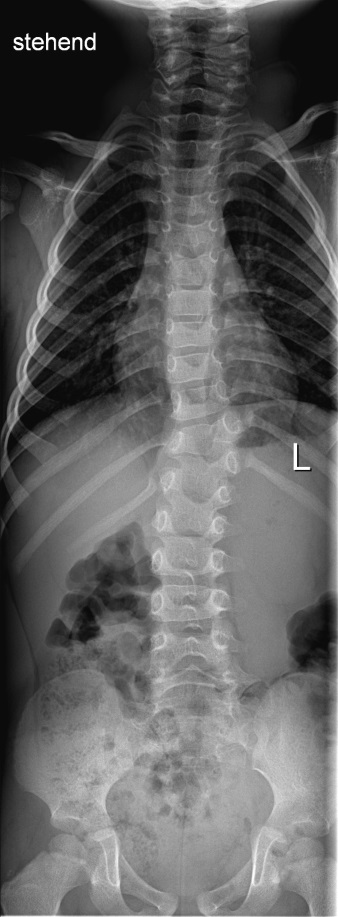

Röntgen.jpg

Röntgenbild vom August 2017, also mit 3 Jahren

Ein normales Röntgenbild im Stehen wurde im August 2017 gemacht. Dies war auch ausschlaggebend für das angeordnete MR.